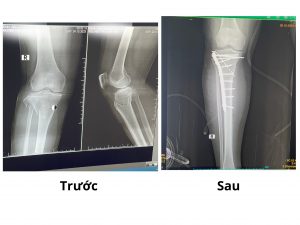

Bệnh nhân 59 tuổi sau TNGT được đưa đến Bệnh viện Đa khoa Bố Hạ trong tình trạng sưng nề cẳng chân phải, đau, mất vận động chân phải. Bệnh nhân được sơ cứu ban đầu, khám lâm sàng kết hợp kiểm tra đánh giá tổng thể, chụp X-quang xương cẳng chân phải, phát hiện tổn thương gãy kín đầu trên 2 xương cẳng chân phải.

Bệnh nhân được chỉ định mổ cấp cứu kết hợp xương chày bằng nẹp vít bởi các bác sĩ Bệnh viện Đa khoa Bố Hạ và bác sĩ bệnh viện tuyến TW. Sau 2 giờ phẫu thuật, ca phẫu thuật kết thúc an toàn, xương gãy được cố định vững chắc. Hiện tại, sau mổ tình trạng ổn định, phục hồi tốt.